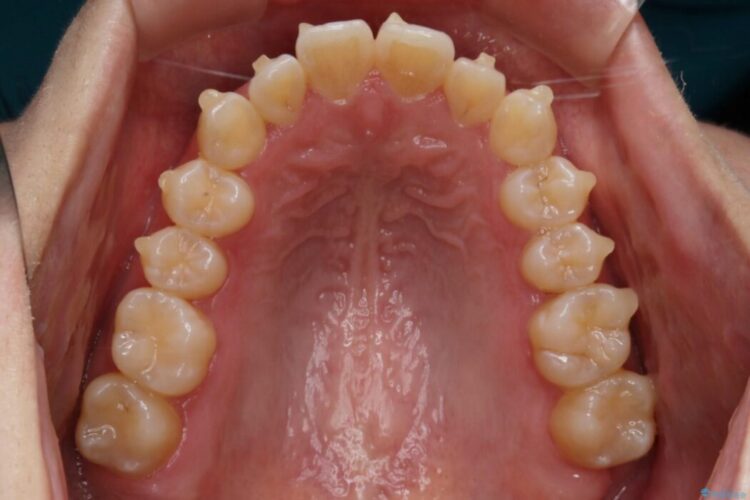

上顎歯列のガタガタを改善したいとのことで来院されました。

前歯の一部に反対咬合が見られ歯列がガタガタしていたためインビザラインでの矯正治療をご提案しました。

また、奥歯の噛み合わせなどにほとんど問題がなかったことからインビザラインのライトパッケージを選択しました。